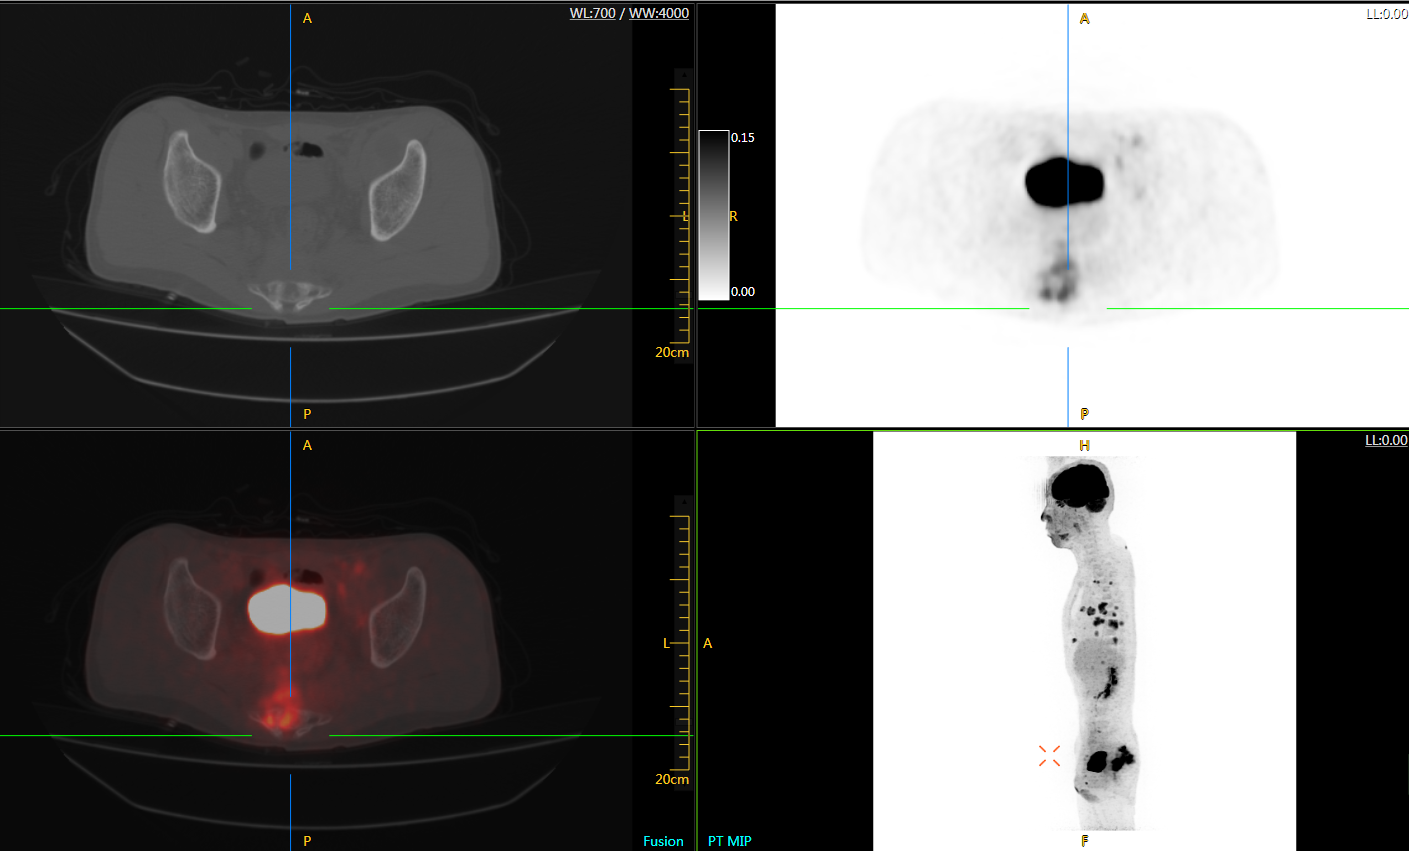

圖例

直腸癌

男,45歲,直腸癌術(shù)后9個(gè)月,發(fā)現(xiàn)肺占位

臨床診斷:直腸區(qū)術(shù)后改變,復(fù)發(fā)伴骶骨受累,雙肺多發(fā)轉(zhuǎn)移